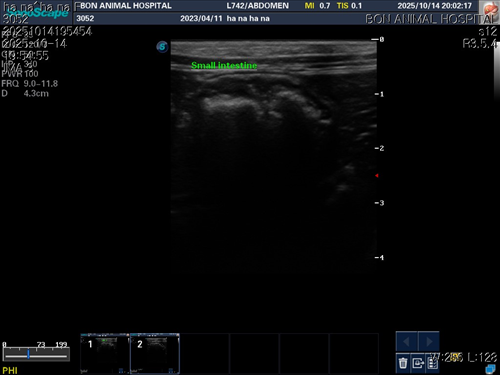

10월 10일 포도를 토해논후로 식욕저하 기력저하가 있어서 동물병원에 방문해서 엑스레이를 찍었는데 우선 지켜보자는 말과 소화제처방과 주사를 맞고 집왔습니다 그 후로도 안먹어서 12일에 동물병원에가서 혈액검사도 하고 수액도 맞았습니다 췌장쪽 수치가 좀 높아서 췌장쪽만 다시 검사했는데 수치는 괜찮았습니다 식욕촉진이랑 소화제처방 받아서 먹이는데 식욕저하도 여전하고 기력이 좀 없고 10일부터 14일까지 대변을 못보고있어서 14일에 병원에 가서 엑스레이랑 초음파를 했는데 장폐색일수도 있다는 말을 들었습니다 초음파상으로는 소장쪽 이물이 의심된다고 하셨어요ㅠ